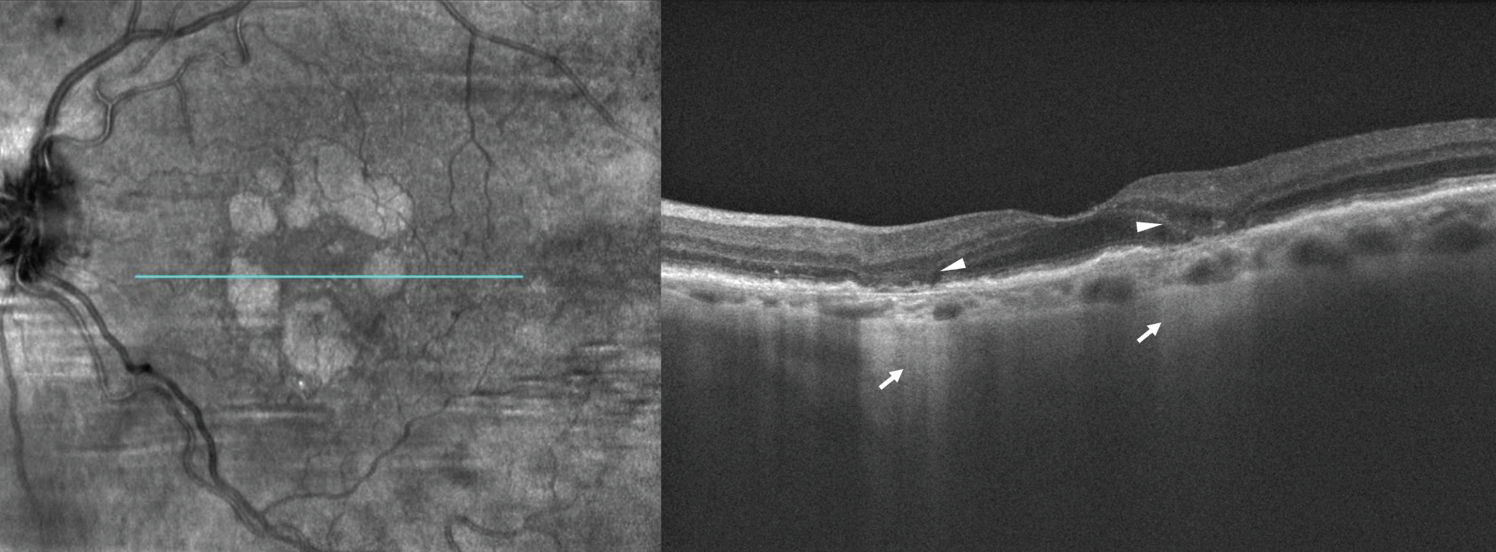

![]() |

| Figure 2. En face optical coherent tomography (left) of the left eye demonstrates multifocal, wreath-like pattern of geographic atrophy wrapping around, but sparing the fovea. Structural spectral domain-OCT (right) reveals hypertransmission of OCT signal through atrophic areas of absent RPE appearing as a bar-code pattern posteriorly (arrows). The diameter of the lesions is greater than 250 µm, meeting the criteria of complete retinal pigment epithelium and outer retinal atrophy (cRORA). Subsidence of inner nuclear and outer plexiform layers and ellipsoid zone disruption overlie areas of RPE atrophy (arrowheads). High-risk features for progression include multifocal GA, foveal-sparing and irregular lesion border. |

Incomplete RPE and outer retinal atrophy (iRORA), defined on OCT as vertically aligned signs of photoreceptor degeneration, RPE attenuation or disruption, and increased signal transmission into the choroid <250 µm in diameter in the absence of an RPE tear.21,22

Complete RPE and outer retinal atrophy (cRORA), when RPE changes and hypertransmission reach 250 µm the lesion is qualified as cRORA (Figure 2 above).21,22 iRORA lesions are known to progress to cRORA lesions at variable rates from months to years.22